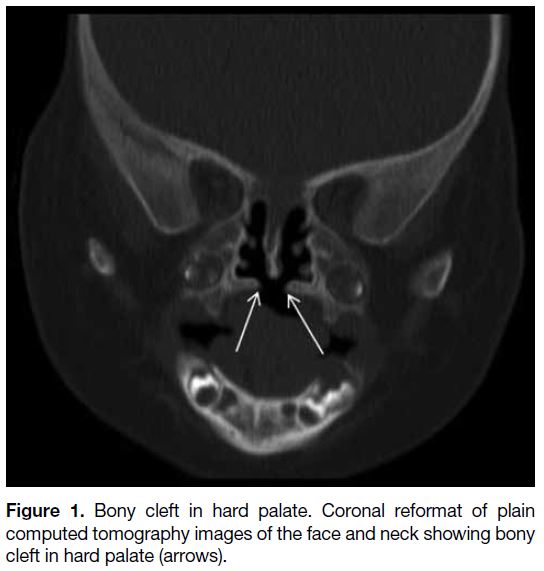

Normally the hard palate should be intact without any

defect. In the case of cleft palate, there will be bony defect

within the hard palate (Figure 1). In cases of Pierre Robin

sequence, cleft palate is associated with micrognathia

Figure 1. Bony cleft in hard palate. Coronal reformat of plain

computed tomography images of the face and neck showing bony

cleft in hard palate (arrows).